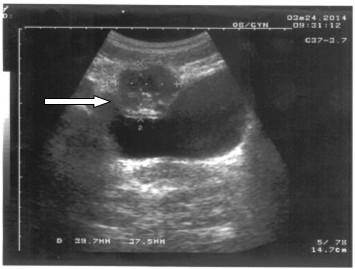

Se presentan las imágenes ultrasonográficas de una paciente femenina, de 33 años de edad, con antecedentes de salud, historia obstétrica G3 P2 A1, con esterilización quirúrgica desde hacía tres años y medio, que requirió asistencia médica por referir dolor de largo tiempo de evolución en bajo vientre, que se incrementaba a las actividades físicas y al acto sexual. Se realizó ultrasonido abdominal que mostró imagen redondeada, mixta, con calcificaciones de 38X42mm en su interior, y que desplazaba la vejiga hacia abajo, sin que se pudiera definir la causa. (Figuras 1 y 2).